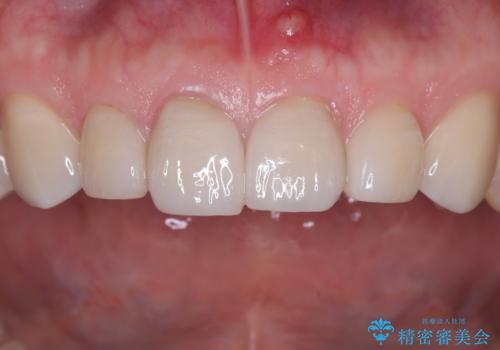

【セラミッククラウン】他院で治療したセラミッククラウンをやりかえたい

- 他院で1年ほど前にセラミッククラウンを入れたそうですが、しばらくしてから歯茎から膿が出てきたそうです。

歯髄診にて歯髄が失活していることが判明したため、クラウンを除去し根管治療を行ってから、再度オールセラミッククラウンを作成しています。

今回のケースはクラウン除去した際に露髄点は認められなかったため、形成時の発熱が原因であったと推測しています。